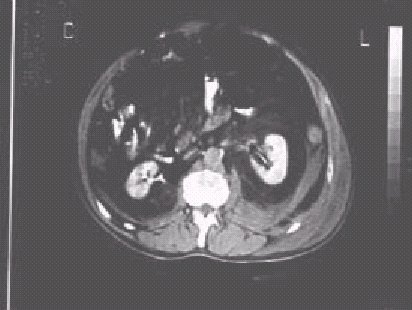

Figura 14.

—Hematoma en región perirrenal izquierda.